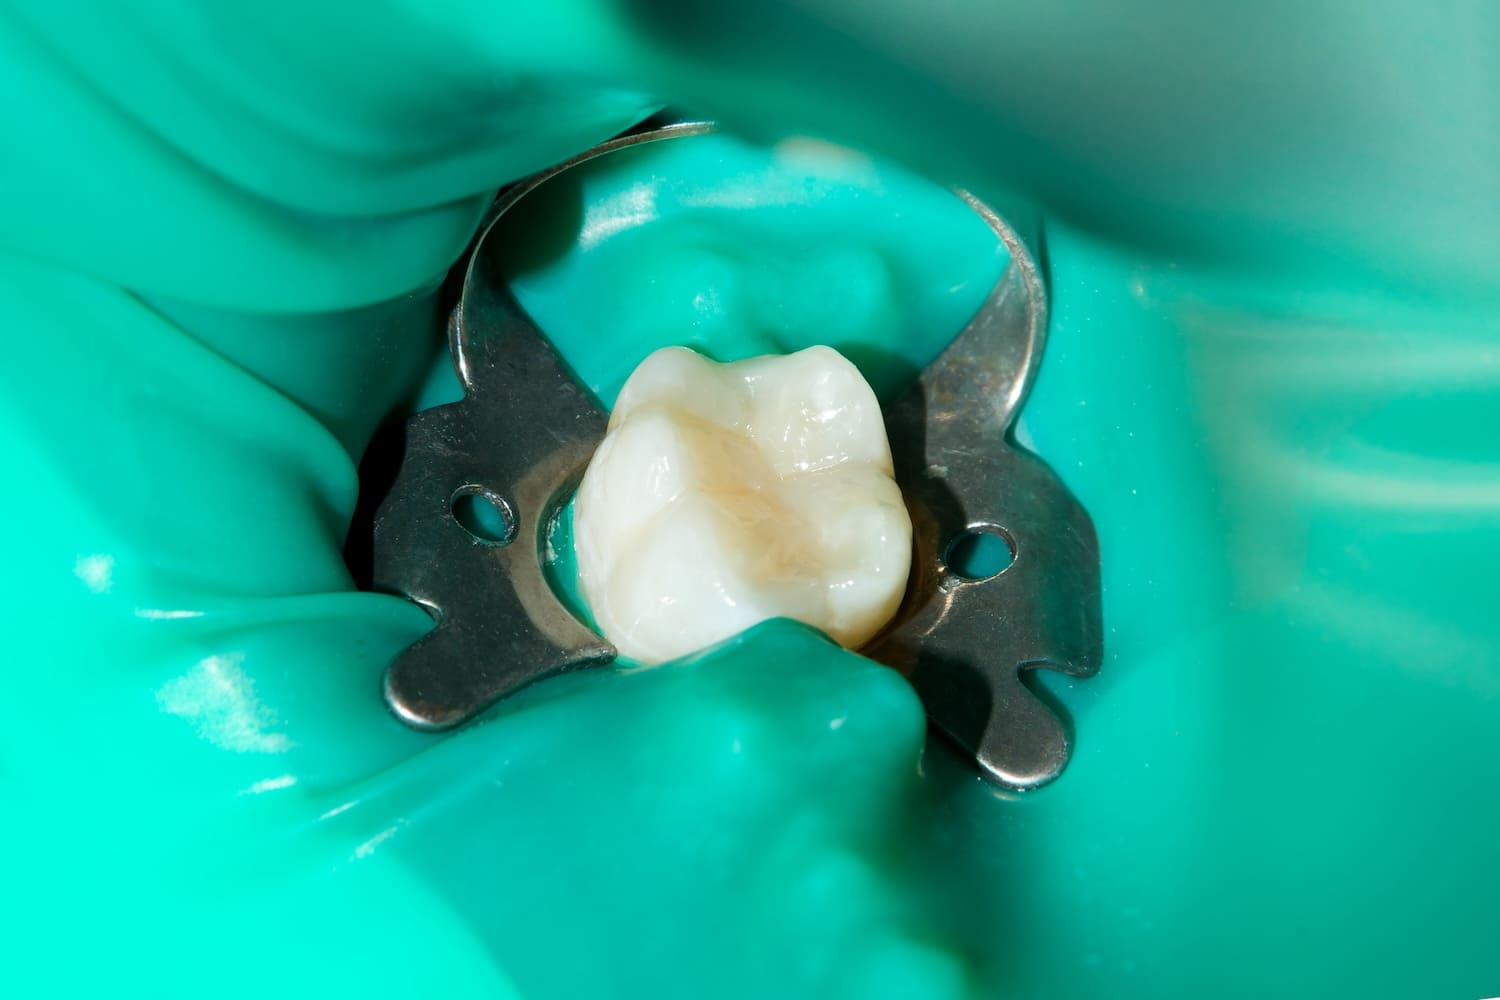

| ラバーダムの使用 (※大臼歯など必要なケースで) |

| 治療中に唾液や口腔内の細菌が根管に入り込むのを防ぎ、感染経路をシャットアウトします。 | 柔軟性と切削能力に優れたニッケルチタンファイル、Uファイル、06C +ファイルなどの専用器具を適切に使い分け、複雑な根管内の清掃を徹底します。 |

| 治療中に唾液や口腔内の細菌が根管に入り込むのを防ぎ、感染経路をシャットアウトします。 |